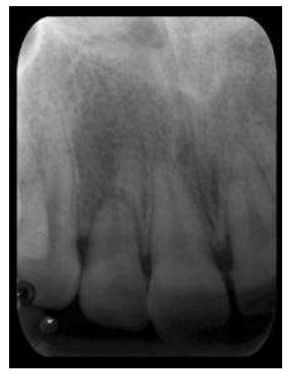

66.24歲女性主訴一個小時前跌倒,撞到上顎前牙,臨床檢查發現右下唇有1.5 cm撕裂傷、右上側門牙動搖度增 加,且超出門齒切緣,根尖片影像如附圖,下列敘述何者錯誤? (A)右上側門牙牙根斷裂 (B)右上側門牙牙冠部須持續追蹤牙髓活性,必要時進行根管治療 (C)水平牙根斷裂,須以不同的X光水平入射角照射,以得知斷裂線位置 (D)水平牙根斷裂之斷裂線越靠近牙根中段預後較差